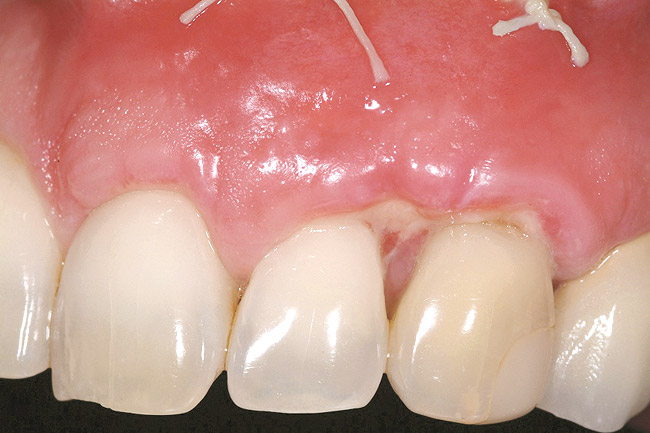

The provisional restoration was an immediate non-functional restoration, and was free of contact in centric occlusion, protrusive, and right and left lateral excursive movements. Figure 29 is the 6-week postoperative view. Note the free gingival margin at the mid-facial point of the left central incisor, and compare that to the pretreatment level seen in Figure 21. The site would be allowed to heal and mature for an additional 6 weeks prior to completion of the final implant-supported restoration.

Figure 29  Case Three 3-month postoperative tissue emergence profiles..

Figure 29